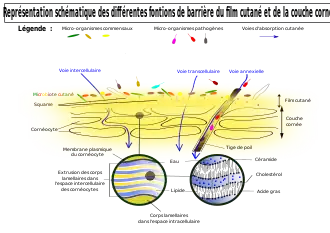

Une phase aqueuse est sécrétée avec la sueur en plus de l'humidification transcutanée (« perte insensible en eau transcutanée » ou TEWL pour « Transepidermal water loss »[33]).

Un film hydrolipidique est constamment sécrété et renouvelé (émulsion sébum-sueur) ; le sébum est excrété par les glandes sébacées. Les lipides (mélange d'acides gras polyinsaturés (25 %), de cholestérol (20 %) et de plus de 40 % de céramides[34] sont produits par les kératinocytes (et régulés par des enzymes dont la phospholipase A2 qui hydrolyse les phospholipides cutanés ; le dérèglement du fonctionnement de cet enzyme participe aux troubles[35] tels que psoriasis, acné, dermatite atopique, érythème dû aux rayons ultra-violets, eczéma, etc. C'est ce « film gras » qui s’étale au niveau du stratum corneum sur la phase aqueuse et produit une couche protectrice et bactériostatique[36] comparable au film oculaire[37]. Il rend toute la peau hydrophobe[37].